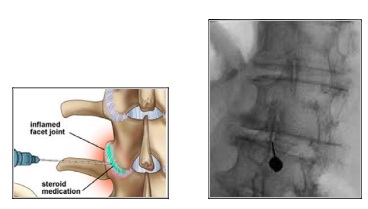

- Τοπική έγχυση στεροειδούς ενδοαρθρικά

Πρόκειται για απευθείας έγχυση στεροειδούς στην κάψα που περιβάλλει την άρθρωση. Διενεργείται κάτω από ακτινοσκοπικό έλεγχο στην αυχενική, θωρακική ή οσφυϊκή μοίρα της σπονδυλικής στήλης. Ανακουφίζει από τον πόνο μέσα σε μερικές μέρες και βελτιώνει την κίνηση.

Διενεργείται με τον ασθενή μπρούμητα, υπό τοπική αναισθησία και ως διαδικασία διαρκεί 10-20 λεπτά.

Μια βελόνα εισάγεται απευθείας στο κατώτερο τμήμα της άρθρωσης, όπου χορηγείται το φαρμακευτικό διάλυμα. Η παρέμβαση δεν χρειάζεται νοσηλεία και ο ασθενής μπορεί να επιστρέψει στην καθημερινότητά του την επόμενη μέρα.